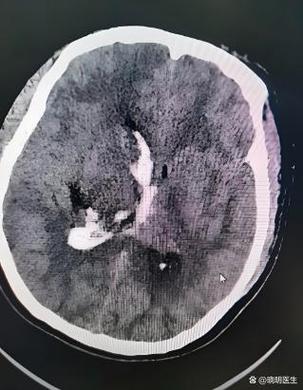

(图片来源网络,侵删)

“梗灶”通常在影像学报告(如CT或MRI)上指“腔隙性脑梗塞”。

- 病因:它是一种特殊的、比较轻微的脑梗塞,通常是由于供应大脑深部小血管(穿通支)的血管壁发生病变(如高血压导致的动脉硬化),导致血管堵塞,造成小范围的脑组织缺血坏死。

- 病灶大小:它的病灶非常小,通常直径在1.5厘米以下,像个小“腔隙”一样。